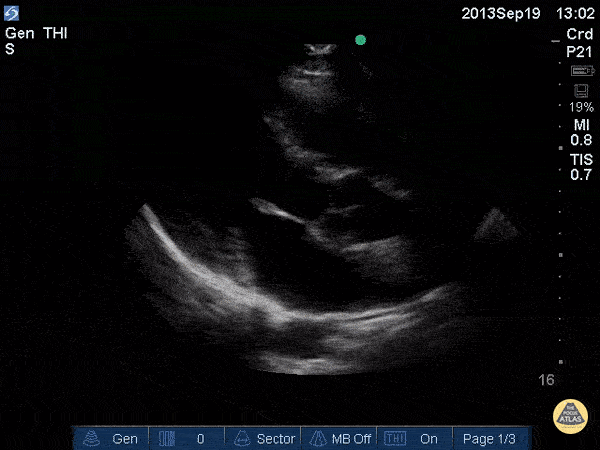

Normal Cardiac Anatomy - Mitral Valve Parasternal Long-Axis View